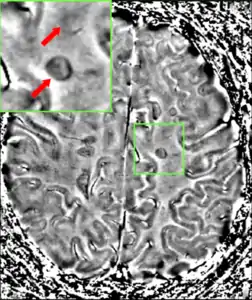

Magnetic resonance imaging (MRI) of the brain and spine may show areas of demyelination (lesions or plaques). Gadolinium can be administered intravenously as a contrast agent to highlight active plaques, and by elimination, demonstrate the existence of historical lesions not associated with symptoms at the moment of the evaluation.[83][84]

Central vein signs (CVSs) have been proposed as a good indicator of MS in comparison with other conditions causing white lesions.[85][86][87][88] One small study found fewer CVSs in older and hypertensive people.[89] Further research on CVS as a biomarker for MS is ongoing.[90]